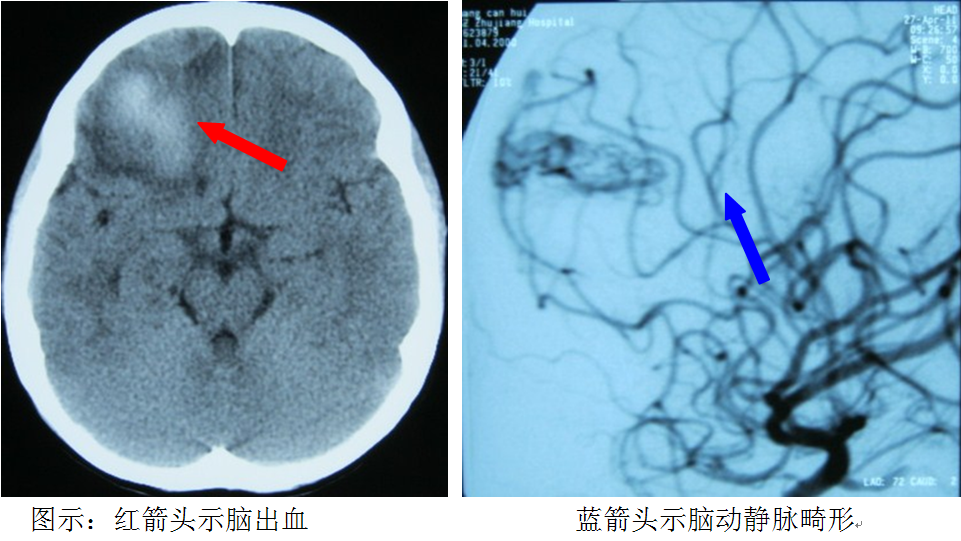

脑动静脉畸形简介

脑动静脉畸形是一种常见的脑血管性疾病,是胎儿期脑血管形成异常的先天性疾患,呈家族性的少见。发病平均年龄约25岁左右,男性发病率大于女性。

脑动静脉畸形最常见危险是脑出血,约占52%-77%,半数以上在16-35岁之间发病。出血与季节无关,通常发生在正常活动时,怀孕期间的出血危险增加。出血前数周至数年内可出现头痛、癫痫(俗称羊癫疯)发作和一些局灶性神经功能障碍样症状。未出血的脑动静脉畸形患者可单独表现癫痫发作、长期的头痛、感觉障碍等神经功能障碍样症状。还有部分脑动静脉畸形可无任何临床症状,或体检时发现或终身不发病。

脑血管的CTA,或头颅的MR,或脑血管的DSA检查,可以确断脑动静脉畸形。因脑动静脉畸形发生脑出血的机率高,且脑出血的致残及致死率高,故当发现脑动静脉畸形时,大多数患者均需要进行积极的治疗,特别是少年及青壮年患者。目前有开颅手术切除、血管内介入治疗及放射学的3种治疗方案,其治疗方案的选择因人而异和因病而异。大部分脑动静脉畸形患者预后良好,治疗后发生脑出血的风险明显降低。(神经外科 龙青山)